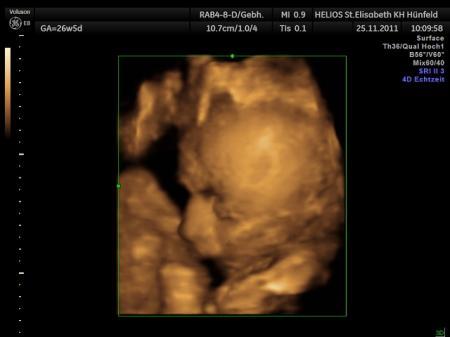

Ja vielen lieben Dank für die Idee und die Organisation :D Hab aber leider noch kein Paketchen bekommen - hoffe das es bald eintrifft - naja wenn nicht hab ich wenigstens Spaß beim lesen was Ihr so bekommen habt - das schönste Geschenk für dieses Jahr trag ich sowieso unter meinem Herzen :D VlG. Änni, Oli und klein Eric im Bauchi

Bild zu